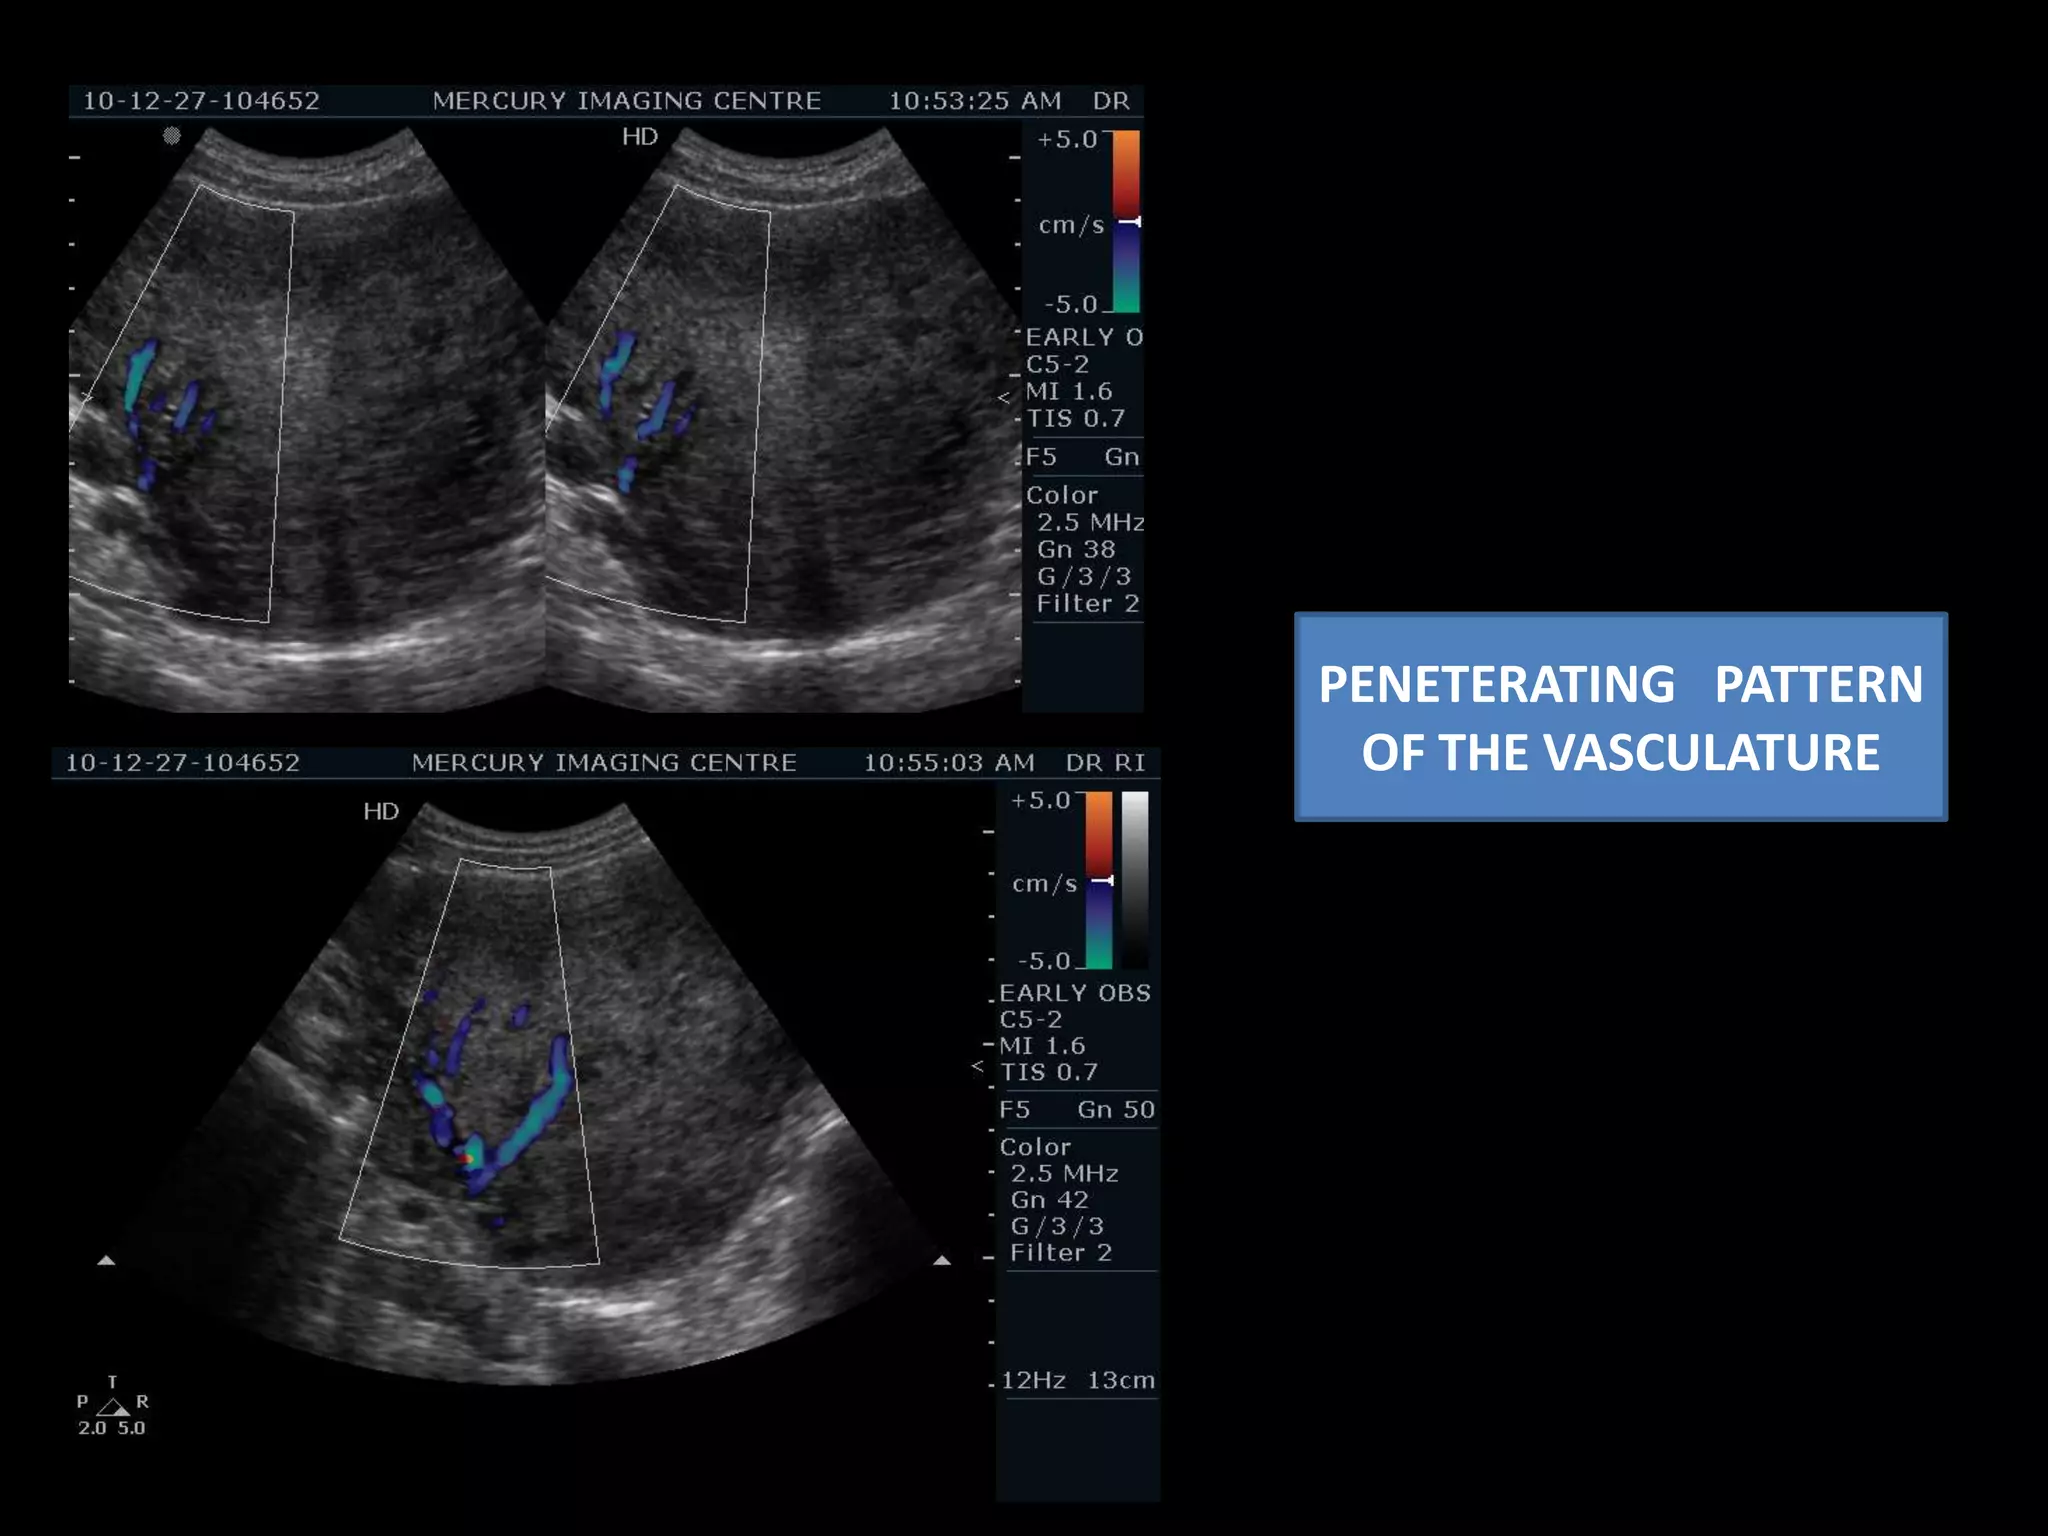

Intramyometrialpeneteratingvascularity.

G sac – 5wks with                    ? Viability----Follow up advised . INCREASED INTRAMYOMETRIAL   VASCULATURE PENETERATING PATTERN

CONGESTED TORTUOUS VESSELS – INTRAMYOMETRIAL . PENETERATING PATTERNFOCAL HYPOECHOIC AREAS APPRECIATED IN THE MYOMETRIUM WITH DEFINED BORDERS – CORROBORATIVE WITH  SMALL LEIOMYOMA.

PENETERATING   PATTERN OF THE VASCULATURE

G sac –5wks with ? Viability----Follow up advised . INCREASED INTRAMYOMETRIAL VASCULATURE PENETERATING PATTERN

CONGESTED TORTUOUS VESSELS– INTRAMYOMETRIAL . PENETERATING PATTERNFOCAL HYPOECHOIC AREAS APPRECIATED IN THE MYOMETRIUM WITH DEFINED BORDERS – CORROBORATIVE WITH SMALL LEIOMYOMA.